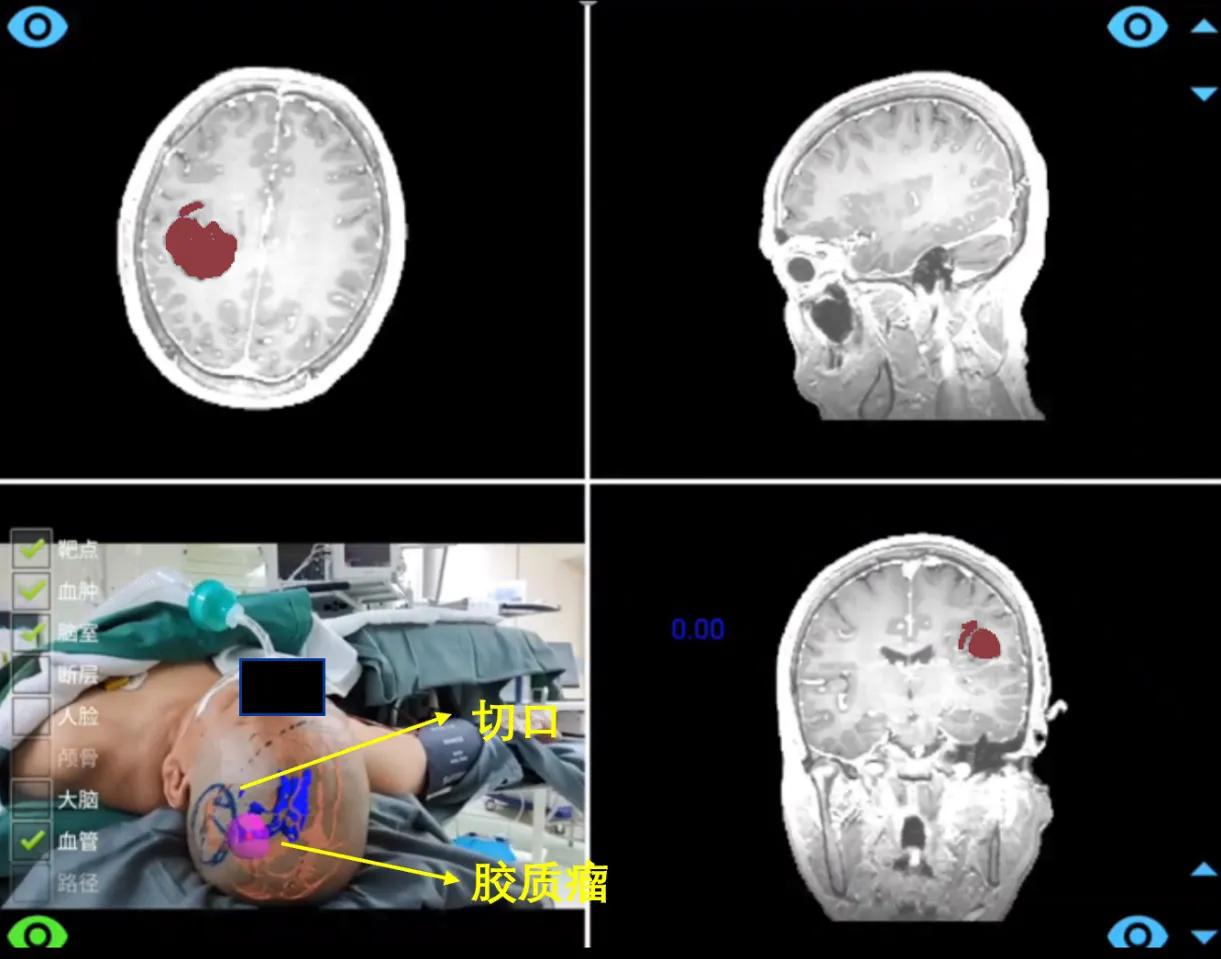

术中,通过SLAM跟踪可在无需头架和参考架情况下,实现增强现实导航。以一位胶质瘤患者为例,医生移动摄像头,系统可实时展示病人颅内的三维结构相对头皮的位置关系,辅助医生快速制定切口。

(术前切口制定)

(术中导航)